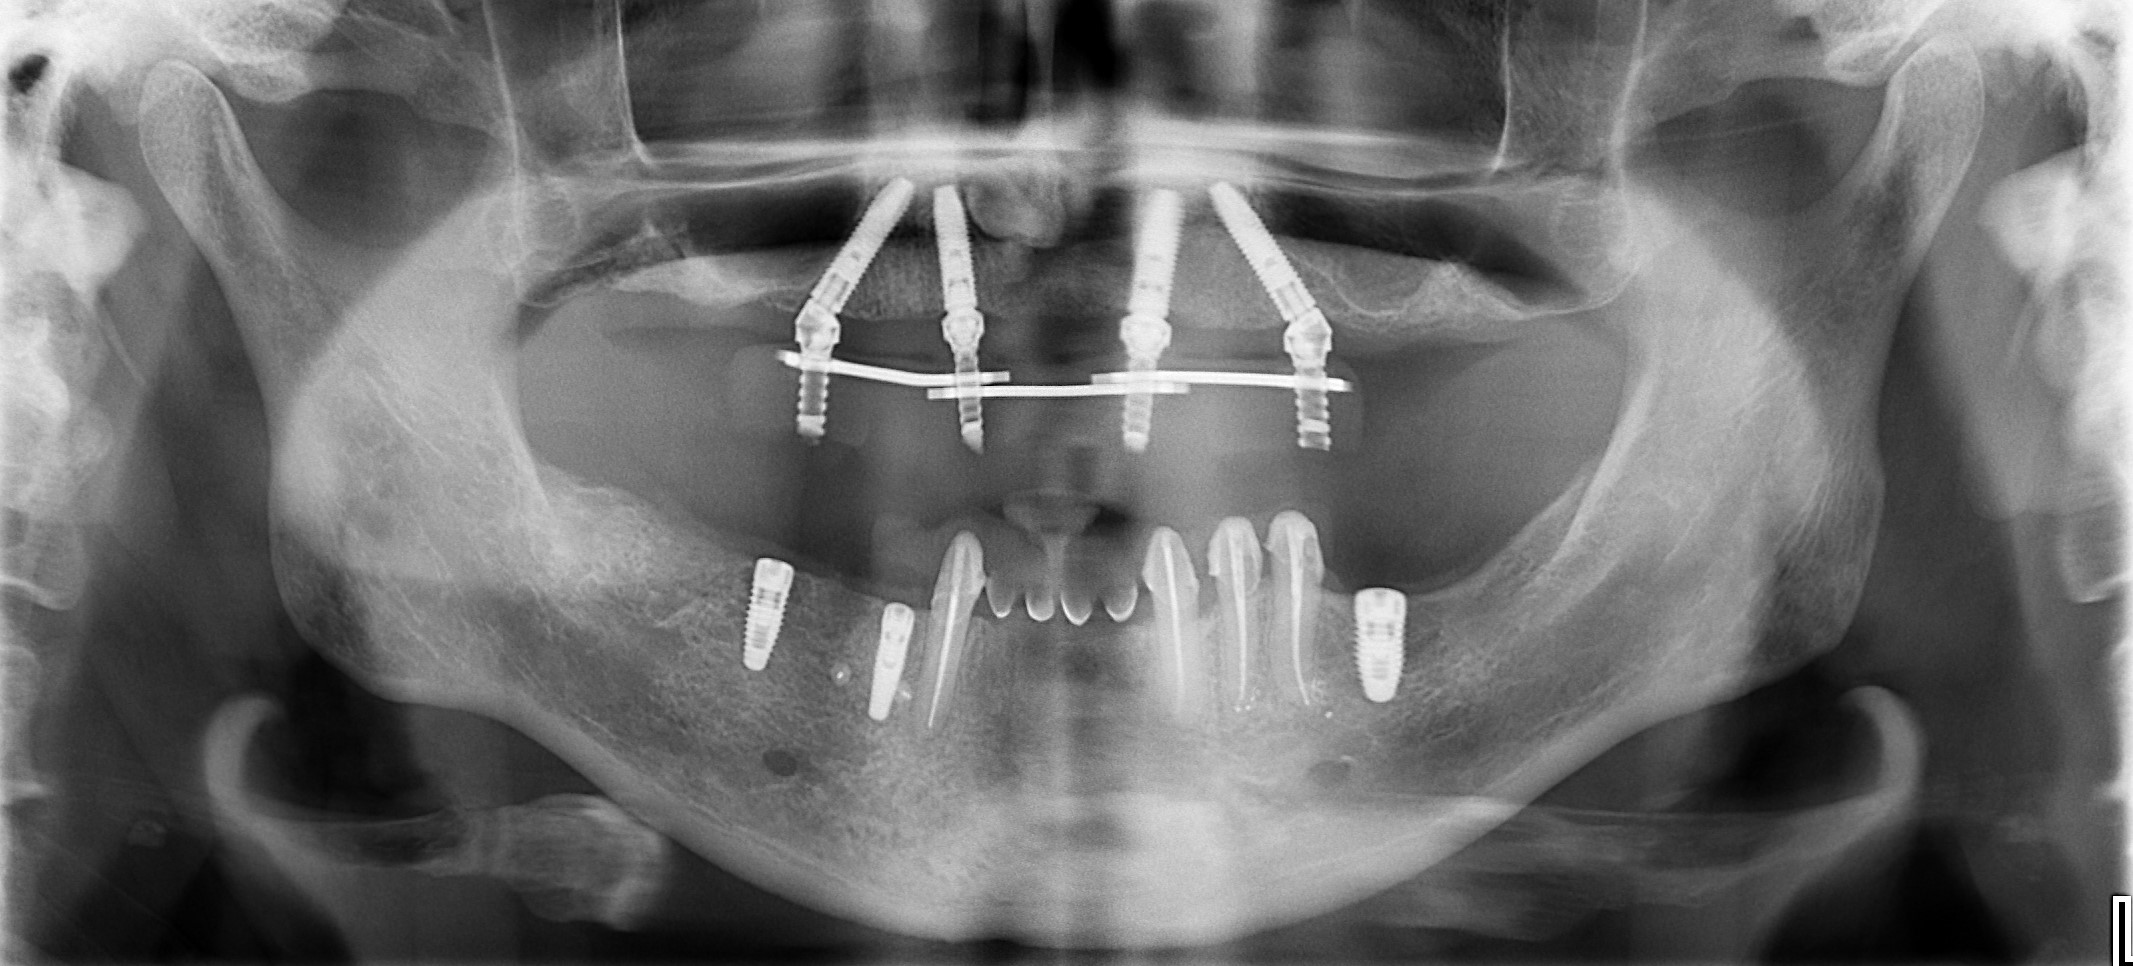

На панорамной рентгенограмме отмечаются: пневматизация верхнечелюстных синусов, значительная утрата пародонтальной поддержки зубов 2.7, 3.1, 4.1, 4.2, 4.5, 4.7, выраженная атрофия беззубых участков челюсти (рис 4).

Контрольная панорамная рентгенограмма после имплантации и установки временного протеза на верхней челюсти (рис. 38) По плану лечения также на нижней челюсти установили имплантаты в области 3.6, 4.4 и 4.6 зубов. Зубы 3.5, 3.4,3.3 – 4.3 были предварительно восстановлены мостовидными несъемными временными коронками из полиметилметакрилатного материала.

На панорамной рентгенограмме после окончания протезирование с постоянными конструкциями обоих челюстей мы видим стабильный уровень костной ткани вокруг каждых имплантатов и зубов (рис. 50).